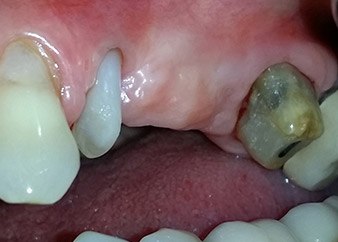

Eine 58-jährige Patientin, die auch eine gute Freundin und ärztliche Kollegin ist, beschwerte sich über Schmerzen und erhöhte Beweglichkeit ihres Brückenpfeilers 24. Es lag auch eine parodontale Entzündung vor, mit Taschentiefen von 7 mm mesiobukkal und mehr als 12 mm distal und einer Furkationsbeteiligung dritten Grades. Darüber hinaus zeigte die Röntgenaufnahme eine großflächige apikale Aufhellung am endodontisch (alio loco) vorbehandelten Zahn 24 (Abb. 1).

Ein Jahr zuvor waren die Zähne 25 und 26 vor dem Einsetzen der Brücke aufgrund traumatischer und endoparodontaler Ursachen extrahiert worden. Eine Paro-Endo-Läsion wurde bei unklarer ätiologischer Hauptkomponente für den Zahn 24 diagnostiziert. Die Patientin machte deutlich, dass sie ihre Pfeilerzähne 24 und 27 behalten und keinen endgültigen oder temporären herausnehmbaren Zahnersatz akzeptieren will. Darum wurde vereinbart, alles zu versuchen, beide Zähne, trotz der nach den radiologischen und klinischen Befunden als schlecht einzustufenden Prognose, zu erhalten.

Einen Monat nach dem Eingriff waren sowohl die Schmerzen als auch die Entzündung an Zahn 24 minimal, die Zahnbeweglichkeit lag jedoch noch bei Miller-Klasse 2. Nach Freilegung und Reinigen des infizierten periapikalen und periradikulären Gewebes wurde das Ausmaß des Knochendefizits deutlich (Abb. 2 und 3).

An der bukkalen Wurzel fehlte der gesamte vestibuläre und distale Knochen. Das Attachment beschränkte sich weitgehend auf die palatinale Wurzel, was die anfängliche schlechte Prognose unterstreicht. Auch Zahn 27 wies ein verringertes horizontales Attachment (vgl. Abb. 12) und eine kleine apikale Aufhellung (Abb. 1) auf, allerdings ohne klinische Symptome.